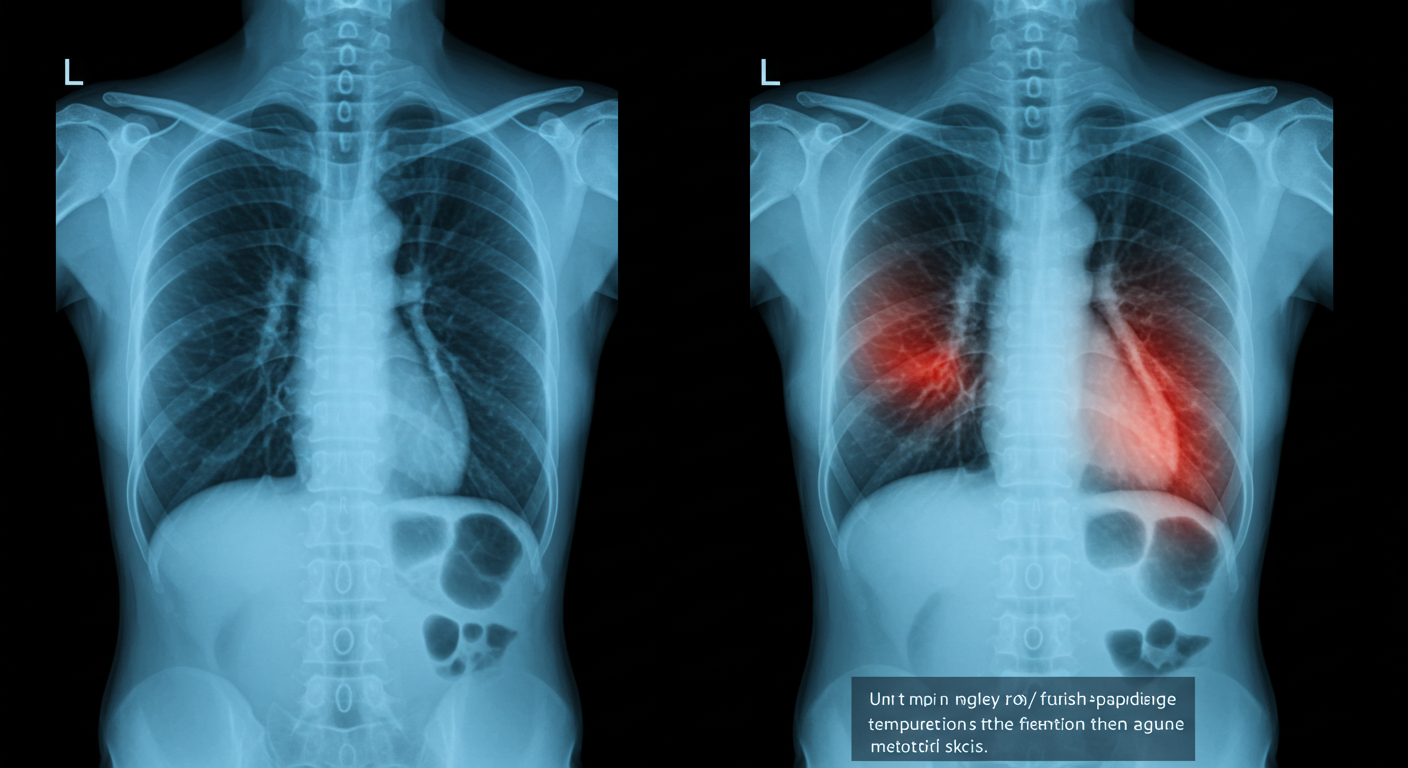

폐렴 초기 증상 및 원인

폐렴은 특히 겨울철이나 환절기에 자주 발병한다. 그 대표적인 증상은 기침이나 가래, 흉통, 고열, 오한, 호흡곤란 등으로 나타나며, 증상이 심할 경우에는 입원을 해서 치료를 받아야 할 수도 있다. 이중에서도 폐포에 염증이 생기면서 산소와 이산화탄소 교환이 어려워지며, 피로와 무기력감을 동반할 수 있다는 점이 특징이다. 특히 65세 이상의 고령자나 면역력이 아직 발달하지 않은 유아, 만성질환자, 면역 저하자에게는 폐렴이 빠르게 악화될 수 있으므로 조기에 발견하여 각별한 주의가 필요하다.